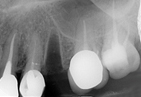

骨脊增厚術,利用骨粉、再生膜等生物科技材料,放入骨脊內,促進缺損處的骨頭再生的術式。先把骨粉放到欲填補的缺損處,然後使用再生膜隔絕表皮軟組織細胞的生長,讓骨粉有時間可以轉化成新生骨。等待約6個月讓骨頭生長,就可以重建喪失的齒槽骨寬度了!

植牙補骨的目的,在於能夠讓植牙擁有厚實的牙床、健康穩固的地基,才能幫助人工植牙使用的更長久,承受更大的咀嚼力量。